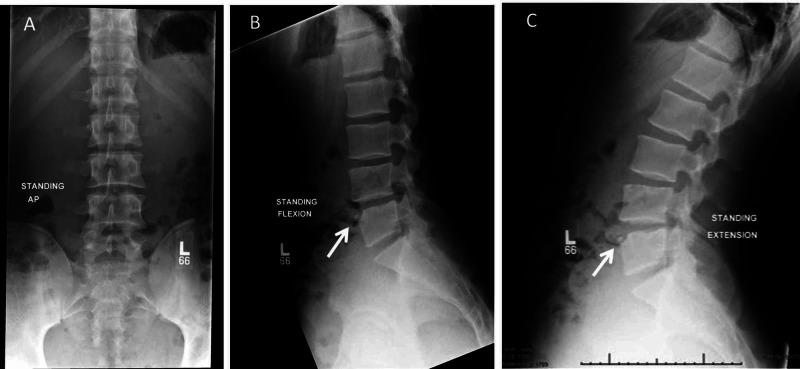

椎体缘。

Limbus Vertebra.

Athletes in their teenage years can present to clinics with back pain, without any history of trauma. Many sports require repetitive spinal extension, which may be pertinent to the evaluation of back pain as a chief complaint. Musculoskeletal and neurologic examinations are crucial in the evaluation of athletes presenting with back pain. Most back pain cases are caused by benign conditions that resolve with conservative treatment. However, radiographic imaging may be appropriate to look for possible spondylolysis in teenage athletes who perform repetitive extension in their sports, and who present with a positive stork test on examination. Limbus vertebra is a condition that can be seen in asymptomatic patients but can also be associated with back pain. Nevertheless, a conservative approach is still appropriate in these cases, with escalation to further testing or imaging only considered for recalcitrant pain. Limbus vertebra is not well known by clinicians and can be misdiagnosed. Therefore, early recognition is crucial to potentially prevent an unnecessary cascade of increasing expenses related to time, effort, medications, and resources to find the diagnosis when conservative treatment is preferred.

摘要

十几岁的青少年运动员可能会在没有任何创伤史的情况下到诊所就诊,主诉背痛。许多运动都需要反复进行脊柱伸展,这可能与以背痛为主诉的评估有关。肌肉骨骼和神经系统检查对于评估出现背痛的运动员至关重要。大多数背痛病例是由良性疾病引起的,通过保守治疗可以缓解。然而,对于在运动中反复进行伸展动作且在检查中鹳试验呈阳性的青少年运动员,进行影像学检查以寻找可能的椎弓根峡部裂可能是合适的。椎体缘离断症是一种在无症状患者中也可见的情况,但也可能与背痛有关。尽管如此,在这些情况下,保守治疗方法仍然是合适的,只有在顽固性疼痛时才考虑进一步检查或影像学检查。临床医生对椎体缘离断症了解不多,可能会误诊。因此,早期识别对于潜在地避免在首选保守治疗时因时间、精力、药物和资源等方面不必要的费用增加而进行的一系列检查至关重要。